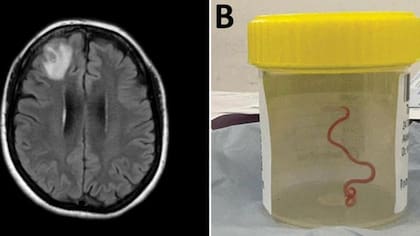

En un caso nunca antes documentado en el mundo, científicos informaron que encontraron un gusano vivo de 8 cm en el cerebro de una mujer en Australia.

La “estructura en forma de cuerda” fue extraída del lóbulo frontal lesionado de la paciente durante una cirugía en Canberra el año pasado. “Definitivamente no era lo que esperábamos. Todo el mundo quedó en shock”, dijo la doctora Hari Priya Bandi, la neurocirujana que operó a la paciente.

Pero la causa de su trastorno solo fue revelada con el bisturí de la doctora Bandi durante una biopsia en junio de 2022. Los médicos dijeron que el parásito rojo pudo haber estado vivo en el cerebro de la mujer hasta por dos meses.

Después consultó a su colega Sanjaya Senanayake, especialista en enfermedades infecciosas, sobre lo que deberían hacer. “Todos en ese quirófano sufrieron el shock de su vida cuando [la cirujana] tomó unas pinzas para detectar una anormalidad y la anormalidad resultó ser un gusano vivo, de color rojo claro, de 8 cm, que se retorcía”, dijo la doctora Sanjaya Senanayake, especialista en enfermedades infecciosas del Hospital de Canberra.